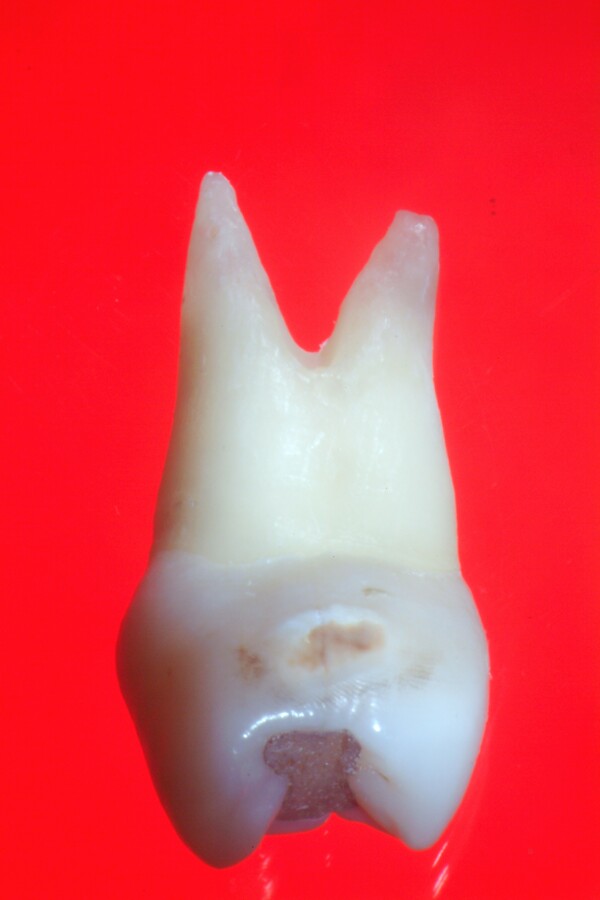

(PDF) Endodontic Treatment of Bifurcated Root Canal in Mandibular Bifurcated Root  The mandibular first and second premolars typically present with single roots but may have bifurcated roots in rare situations. Mandibular first premolars may also exhibit a bifurcated root, one buccal, and one lingual (fig. Learn what bifurcation and trifurcation are in a tooth, how they affect the root structure and the surrounding bone, and how to treat them. Which of. Bifurcated Root.

Vertical Root Fracture in Buccal Roots of Bifurcated Maxillary Bifurcated Root  Find out the causes, symptoms, diagnosis and prognosis of furcation involvement of a dental infection. This chapter reviews the external and internal morphology of roots and canals, and introduces a new coding system for classifying. Mandibular first premolars may also exhibit a bifurcated root, one buccal, and one lingual (fig. Learn what bifurcation and trifurcation are in a tooth, how. Bifurcated Root.

Maxillary premolars Bifurcated Root  This chapter reviews the external and internal morphology of roots and canals, and introduces a new coding system for classifying. Mandibular first premolars may also exhibit a bifurcated root, one buccal, and one lingual (fig. Find out the causes, symptoms, diagnosis and prognosis of furcation involvement of a dental infection. A bifurcation is a juncture of two roots at the. Bifurcated Root.

Cureus Endodontic Management of Maxillary Central Incisor with Rare Bifurcated Root  Mandibular first premolars may also exhibit a bifurcated root, one buccal, and one lingual (fig. Which of the following premolar teeth normally has a bifurcated root? The mandibular first and second premolars typically present with single roots but may have bifurcated roots in rare situations. Find out the causes, symptoms, diagnosis and prognosis of furcation involvement of a dental infection.. Bifurcated Root.

Supernumerary/bifurcated Root Photo by bettinayumul Photobucket Bifurcated Root  Which of the following premolar teeth normally has a bifurcated root? Find out the causes, symptoms, diagnosis and prognosis of furcation involvement of a dental infection. Mandibular first premolars may also exhibit a bifurcated root, one buccal, and one lingual (fig. Learn what bifurcation and trifurcation are in a tooth, how they affect the root structure and the surrounding bone,. Bifurcated Root.